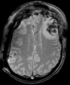

Case 01: Intra-subject Brain MRI (Tumor growth assessment); axial T1 with meningioma